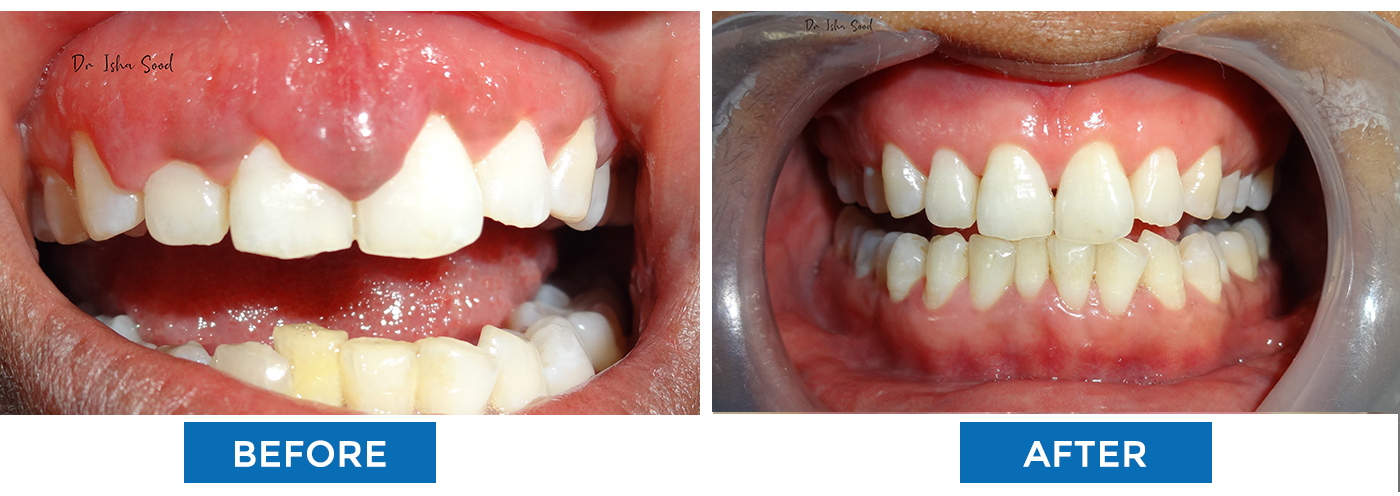

Orthodontic Treatment (Braces)